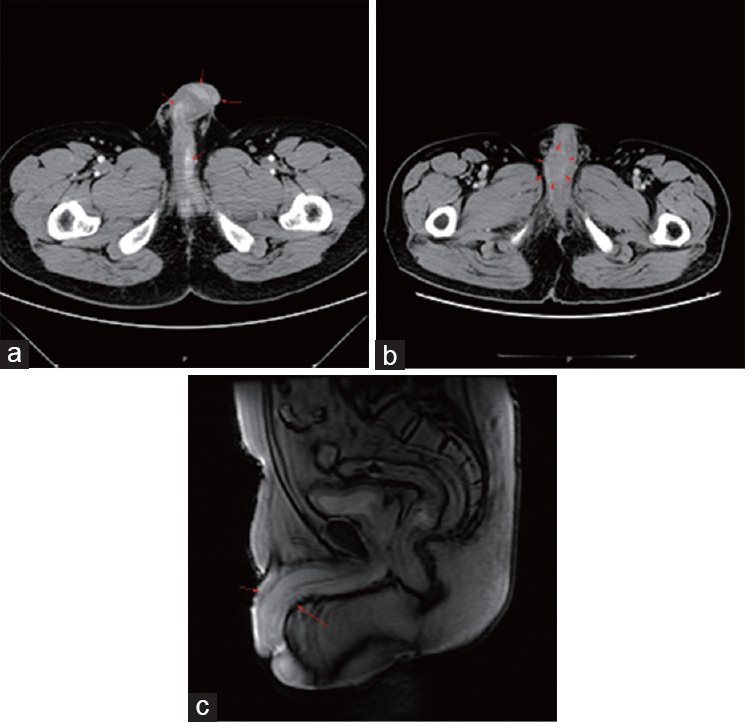

Clinical analysis of secondary penile cancer: a case series at a tertiary referral center in China.

继发性阴茎癌的临床分析:中国一家三级转诊中心的病例系列。